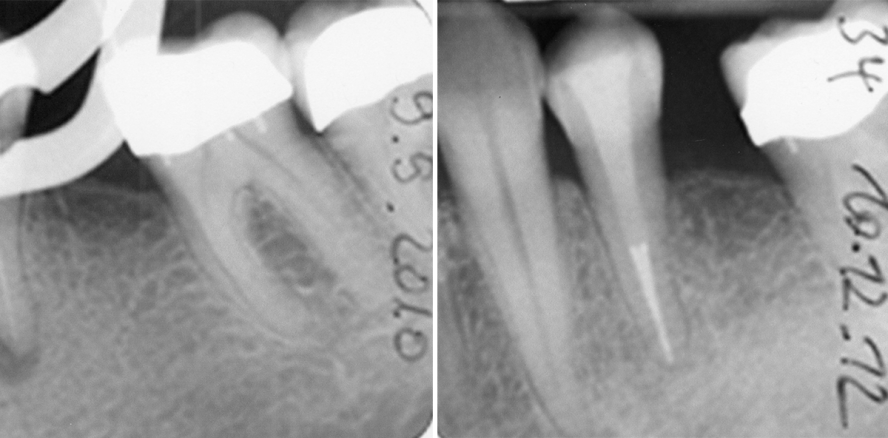

Stehen den endodontisch interessierten und tätigen Kollegen diese (DVT-)Techniken nicht zur Verfügung, dann genügt für den täglichen Gebrauch noch immer der PAI (Score 1 und 2 = „gesund“, Score 3 und schlechter = „krank“), allerdings erweitert um die Definition der European Society of Endodontology (ESE), dass bei einer „unvollständigen Heilung“ die Verbesserung des Scores eine Heilung zu versprechen scheint. Ist jedoch z. B. eine „Verbesserung“ von 5 auf 4 oder ein Bestehenbleiben von 4 zu verzeichnen, so soll dies als Misserfolg gewertet werden, selbst wenn klinische Symptomlosigkeit als auch subjektive Beschwerdefreiheit des Patienten festgestellt werden können. Score 3 steht dann für „Erfolg“, wenn bei „unvollständiger Heilung“ klinische Symptomlosigkeit vorzufinden ist und die Anfangsscores 5 oder 4 waren. Die Erfolgsquoten endodontischer Therapien sind je nach Ausgangslage unterschiedlich. Bei Erstbehandlungen liegen die Quoten höher als bei Revisionsbehandlungen, bei zusätzlichem Vorhandensein periapikaler Läsionen sinken die Erfolgsquoten im Durchschnitt. Die geringsten Erfolgsquoten werden bei wiederholter apikaler Chirurgie erzielt (ca. 37,5 Prozent; Abb. 1–7).

Auch endodontische Revisionsbehandlungen werden nach Möglichkeit in einer Sitzung vorgenommen – wie oben beschrieben u. a. unter Einsatz der aPDT, adhäsiven Endodontie sowie eines aus der Tiefe des Kanalsystems herauskommenden Kompositverschlusses (Abb. 8–11). Dass klinische und röntgenologische Ausgangsbefunde von untergeordneter Bedeutung sein können, zeigen auch die Beispiele in den Abbildungen 12–20.